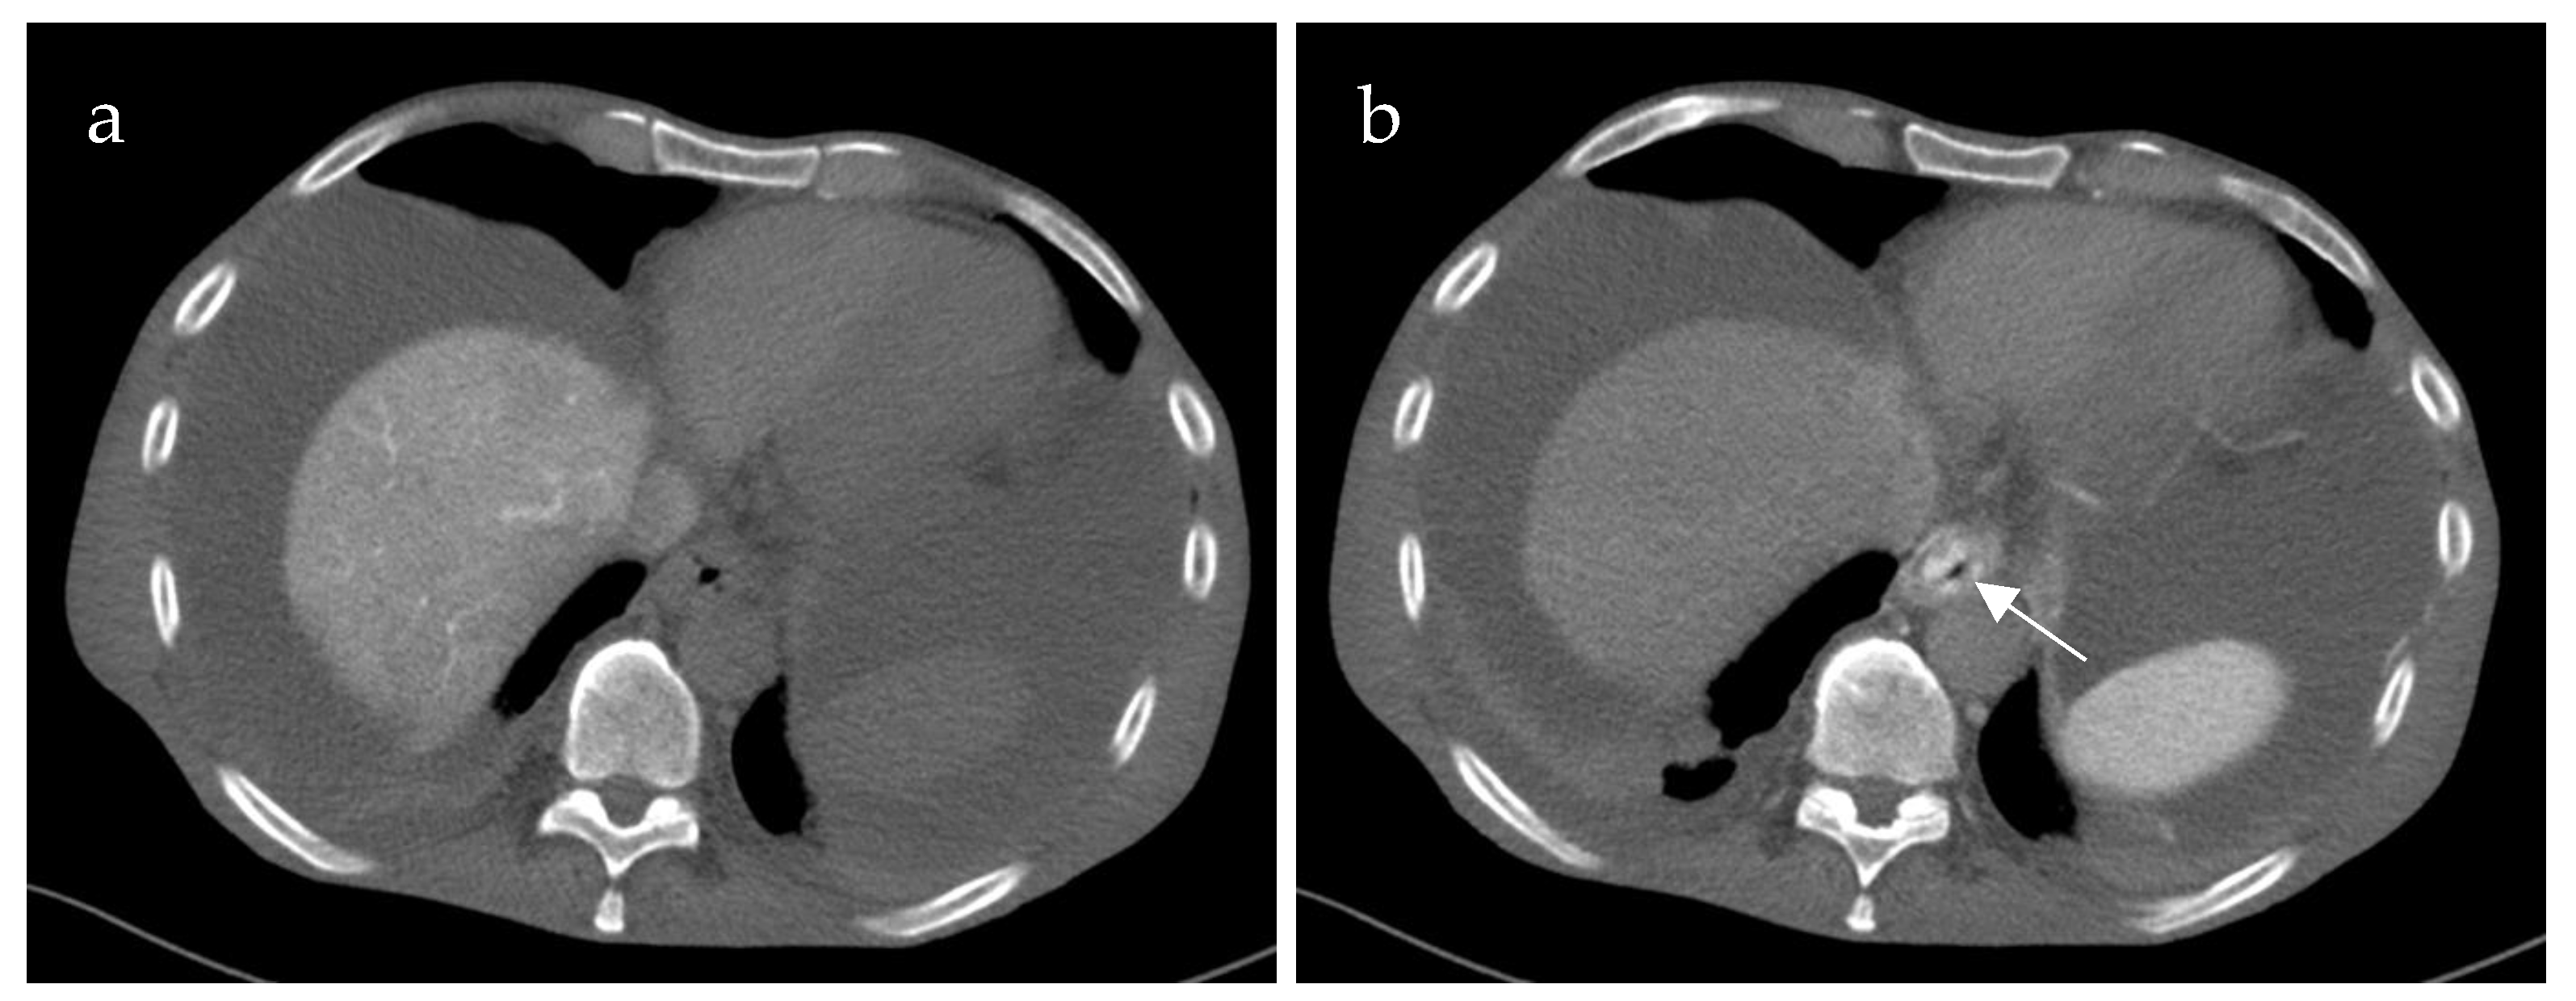

Inflow into esophageal, gastric and small bowel varices differed significantly between patients with PVCT (p = 0.021, p = 0.016 and p = 0.031, respectively) compared to patients without PVCT. In patients with PVCT, esophageal varices were fed solely by the SV in 75% (n = 9, example shown in Figure 3), solely by the mesenteric vein system in 8% (n = 1) and by both systems in 17% (n = 2, example of this rare case shown in Figure 4). Patients without PVCT showed a more equal distribution of inflow hemodynamics: esophageal varices were fed by solely the SV system in 22% (n = 2), by solely the SMV system in 22% (n = 2) and by both systems in 56% (n = 5, example of this is shown in Figure 5). In patients without PVCT, gastric varices were fed by the SV (22%, n = 2), by the SMV (11%, n = 1) or both (22%, n = 2). In contrast, 59% of the patients with PVCT (n = 7) showed gastric varices which were fed only by the SV. In 33% of cases (n = 4), both the SV and SMV drained into gastric varices. No inflow into gastric varices solely from the SMV was detected. These results were statistically significant (p = 0.016).

Figure 4. Computed tomography mesenterico-portography of a 24-year-old male patient with portal hypertension and portal vein thrombosis involving the confluence. Axial (a) and coronal (b) image after contrast injection into the superior mesenteric artery shows large contrasted periesophageal varices (white arrow) fed by the mesenteric system.